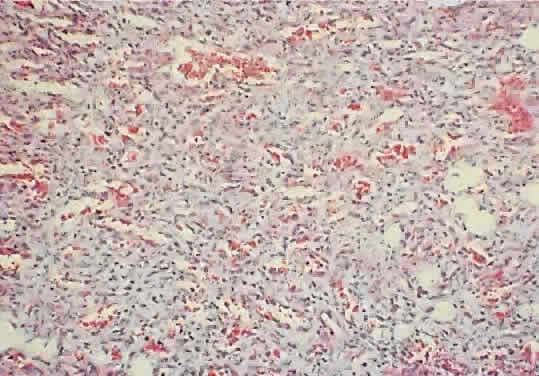

may be necessary for definitive diagnosis. As noted, the histology

of capillary hemangioma evolves with its natural history. At initial

presentation, the lesion consists of lobular proliferations of plump endothelial

cells that circumscribe small vascular spaces (Fig. 10). Electron microscopy shows pericytes about the endothelial cells, but

smooth muscle is lacking.69 Involuted lesions show diminished endothelial cellularity and islands

of fibrofatty infiltration.61  Fig. 10. A capillary hemangioma consists of sheets of plump endothelial cells that

and bilateral vision loss.77,78 When the tumor's histology (see Fig. 10) and hemodynamic continuity are considered, it would seem that any intralesional

injection is, to some degree, an intravascular one, regardless